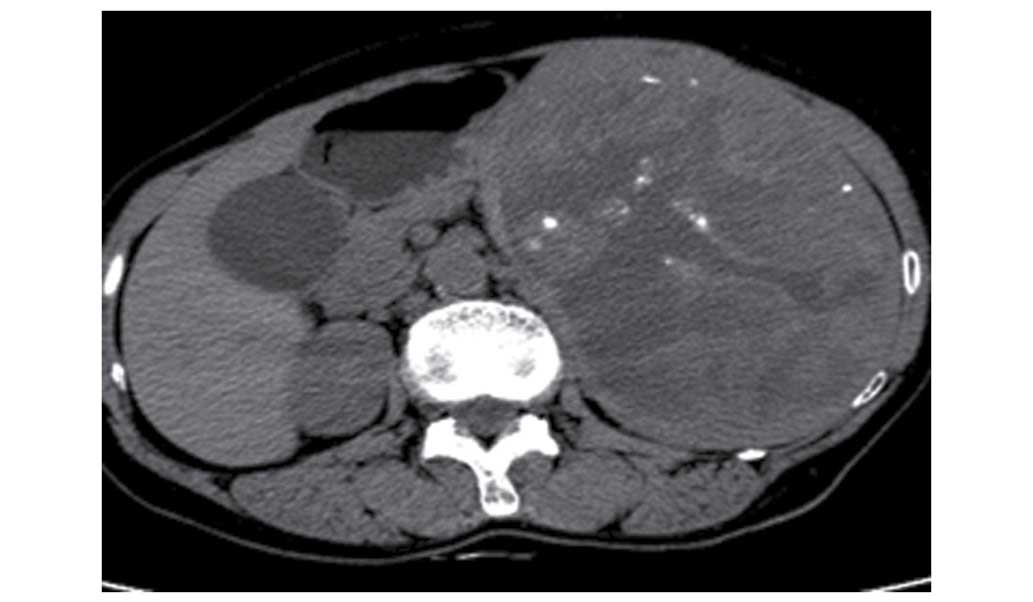

In July 2013, an abdominal mass was found in a 64-year-old woman (who did not present obvious symptoms at that time) at a health center in Suzhou, China. The patient was then hospitalized in the Affiliated Wujiang Hospital of Nantong University (Suzhou, Jiangsu, China) for further examination by computed tomography (CT). Non-enhanced CT showed that this mass measured 190×124 mm, and was located in the spleen where a massive shadow was visible. The lesion manifested as a lower hybrid density shadow and calcification, with clear borders (Fig. 1). Moderate inhomogenous enhancement was found at the arterial phase (Fig. 2) and inhomogenous continuous enhancement was found at the venous phase (Fig. 3) following gadolinium administration, and a delayed CT scan showed that the lesion was significantly enhanced (Fig. 4).

Figure 1.

Non-enhanced computed tomography scan showing a 190×124-mm mass located in the spleen, where a massive shadow was visible. The lesion was manifested as a lower hybrid density shadow and calcification, with clear borders.